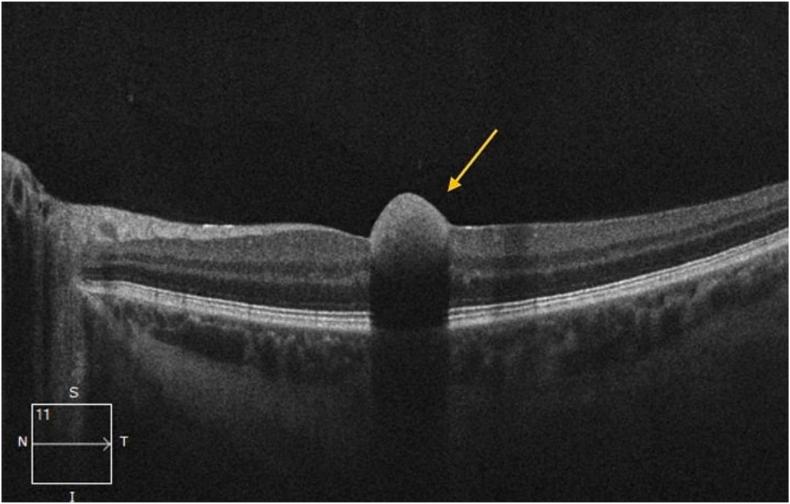

A 27-year-old male with no prior medical history presented with a one-day history of central vision loss in his left eye. Funduscopic evaluation showed a central macular hemorrhage in the left eye and bilateral nerve fiber layer hemorrhages and blot hemorrhages. Fluorescein angiography showed multiple hemorrhages without vascular occlusion or neovascularization, features indicative of anemic retinopathy. Laboratory evaluation demonstrated severe anemia (hemoglobin 6.7 g/dL), with an otherwise unremarkable metabolic and coagulation profile. Given these findings, an underlying hematologic or oncologic disorder was suspected, prompting further systemic evaluation. Imaging revealed a large anterior mediastinal mass, and biopsy confirmed a nonseminomatous germ cell tumor. The patient underwent chemotherapy with cisplatin, etoposide, and bleomycin, later transitioning to VIP (ifosfamide, etoposide, and cisplatin) due to suspected pulmonary toxicity. Patient responded well to treatment; his anemia gradually improved, and alpha-fetoprotein levels significantly declined. Following treatment, the patient reported no ongoing visual disturbances.

Anemic retinopathy can be the initial presentation of an underlying malignancy. Recognizing ophthalmologic findings as potential indicators of systemic disease is critical for early diagnosis and timely intervention in cases of occult malignancies.